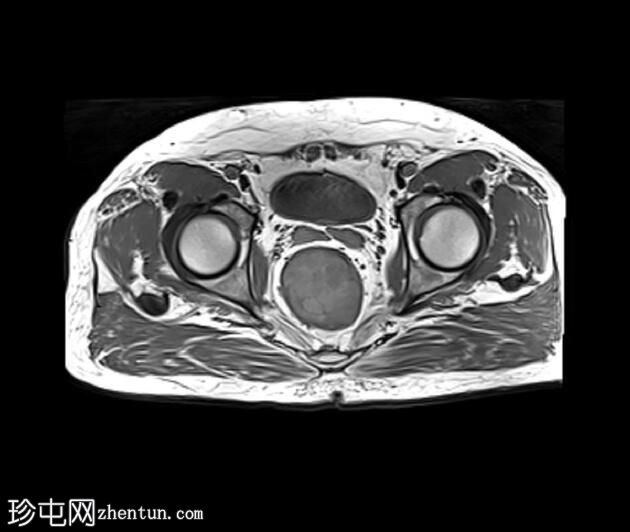

MRI

1.jpeg

冠状位PD加权像

脂肪抑制像

可见一不规则分叶状肿块,累及直肠中段和远端,头尾方向长约7 cm,下缘距肛缘约2.5 cm。在T1加权像和T2加权像上,该病灶相对于骨骼肌均呈高信号。 PDFS(脂肪抑制)图像显示持续高信号强度,提示存在黑色素和/或出血成分。

增强扫描显示病灶内呈不均匀强化。直肠下段7点钟位置的系膜筋膜受累。后方系膜可见少量淋巴结。未见邻近器官侵犯。